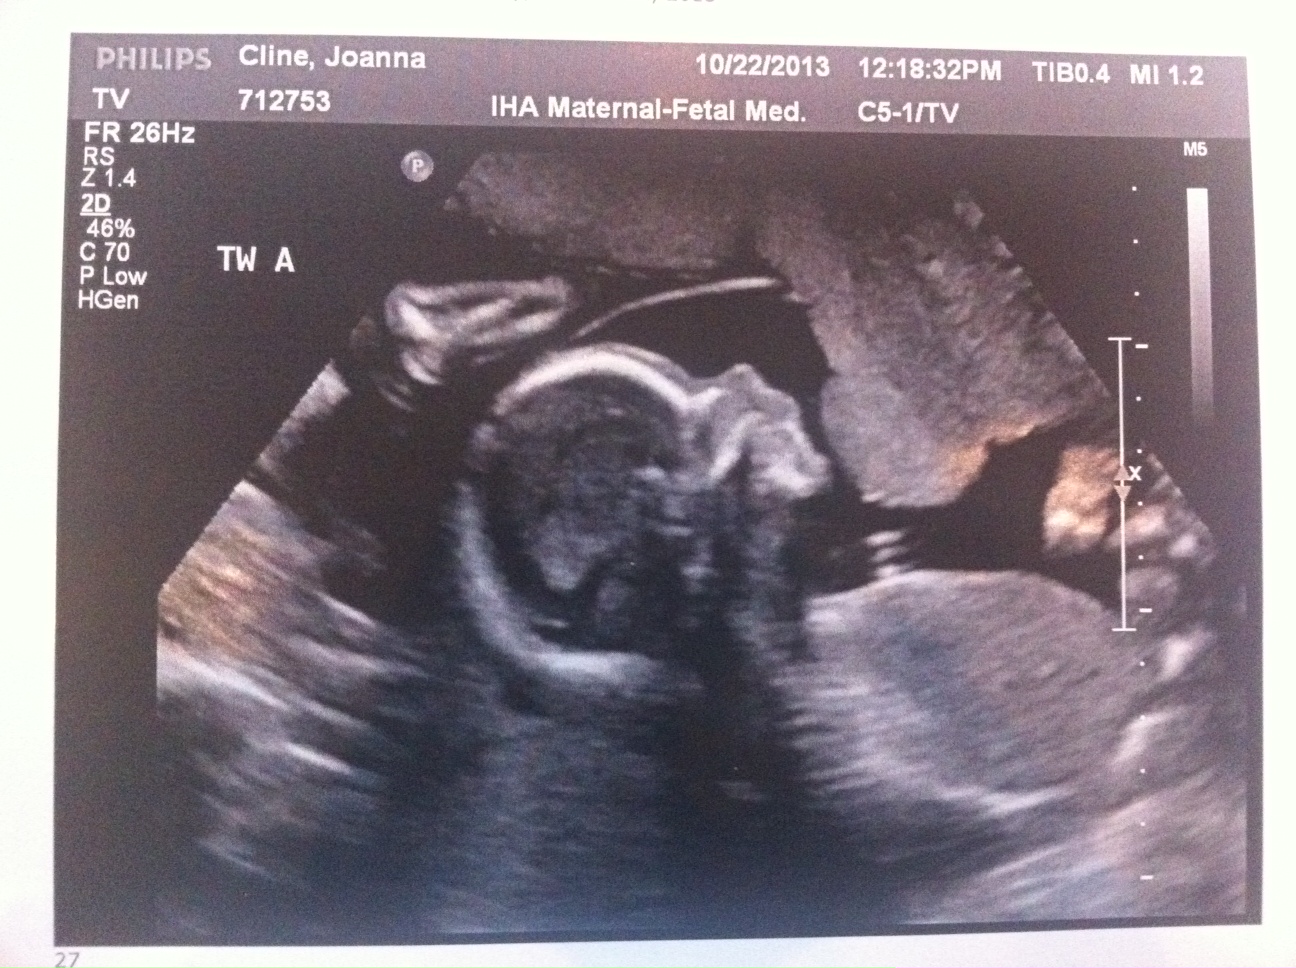

Everything still looks great. The triplets are growing but we won’t have another growth scan until my 22wk appointment. Heart beats look good and it’s clear they’re getting bigger (Today’s pictures attached.)

I’m feeling movement but mostly from triplet B. My dr said to just give it a few weeks and it will feel like a conga line in my belly.